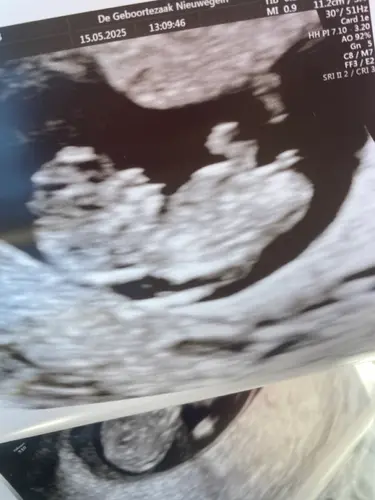

Ik zie dat je ook in de geboortezaak bent geweest. Woon je ook in Nieuwegei ...

Uhm 3,4 mm staat er op mn echo foto, het normale is 3.0 dus veel is het niet maar toch馃ス

Hey lief dat je het vraagt, nu was de nekplooi 3.1 ipv 3.7 , nogsteeds een verhoogd risico waardoor ze de vlokken test aanboden om te doen,